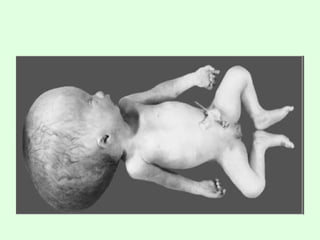

Spina bifida is a developmental birth defect

caused by incomplete closure of embryonic

neural tube.

Cystic expansion of 4th

ventricle in the

posterior fossa

Developmental failure of roof of the 4th

ventricle during embryogenesis.

90% have hydrocephalus.

Prominent occiput.

DANDY WALKER SYNDROME